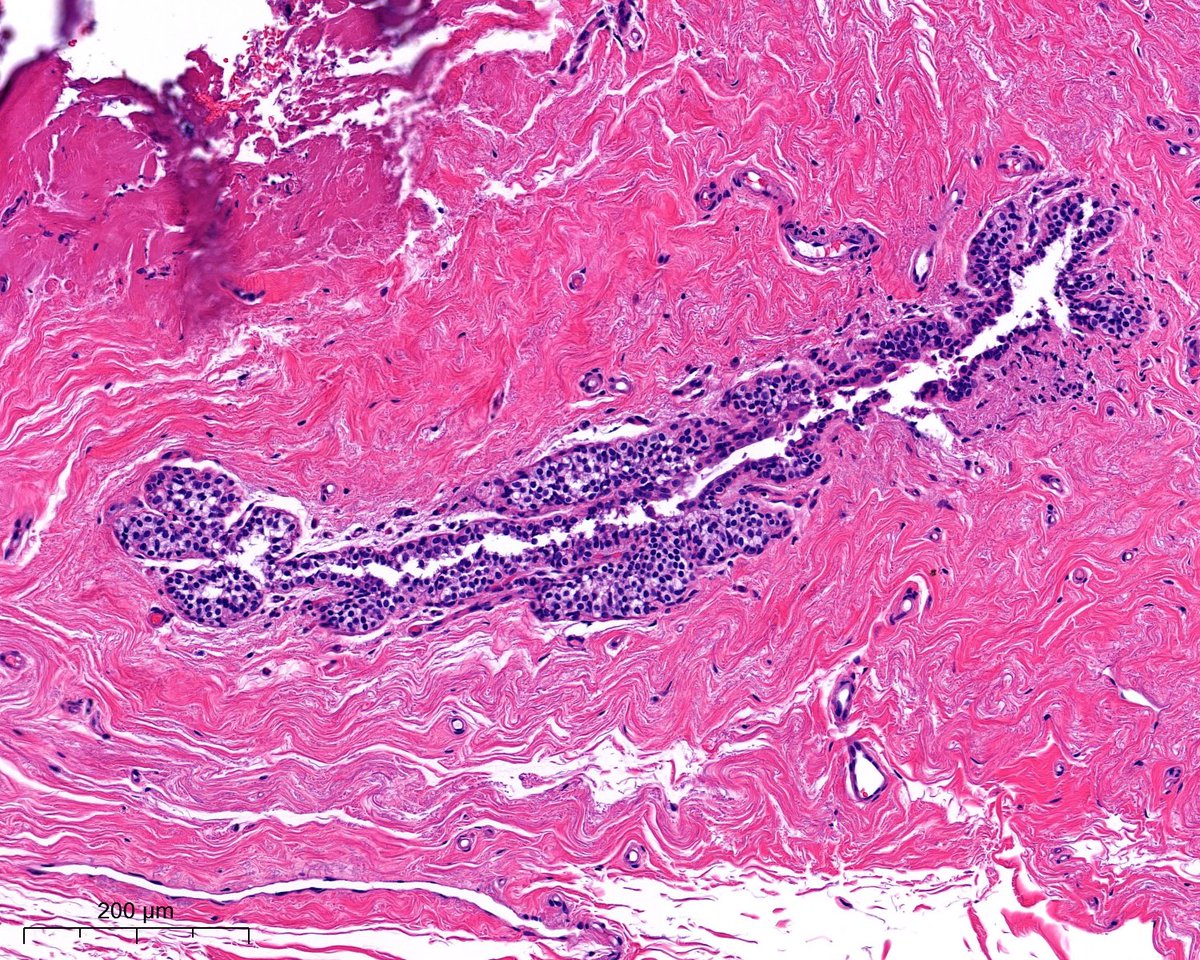

1/7 #GIpath 6th decade female. Very unusual case. Sigmoidectomy + Liver nodule excision. Dx: Neuroendocrine carcinoma with squamous differentiation vs. poorly differentiated colonic carcinoma with neuroendocrine and squamous differenitation!